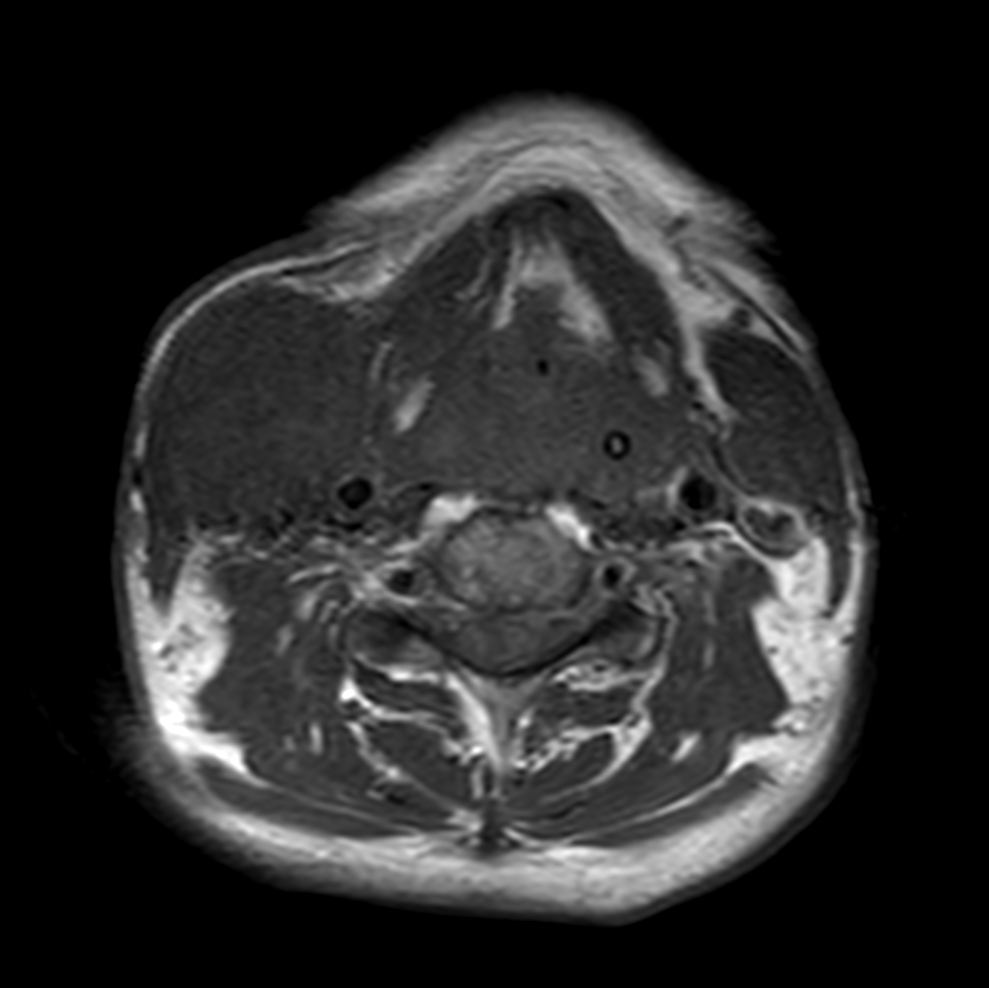

Axial T1w TSE